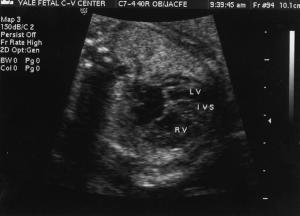

CC is a 31 year old primigravida who was referred for ultrasound at a community hospital due to suspected cardiac anomalies noted on a screening sonogram at her doctor's office. Due to concern about a probable cardiac abnormality an amniocentesis was performed at the local hospital.